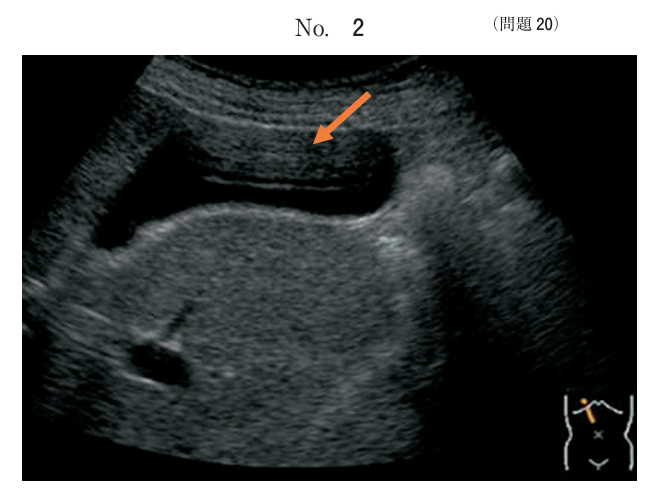

午前/問題20

胆囊の超音波像別冊No. 2 を別に示す。矢印で示すアーチファクトの要因はどれか。

1.鏡面現象

2.多重反射

3.音響陰影

4.サイドローブ

5.後方エコーの増強